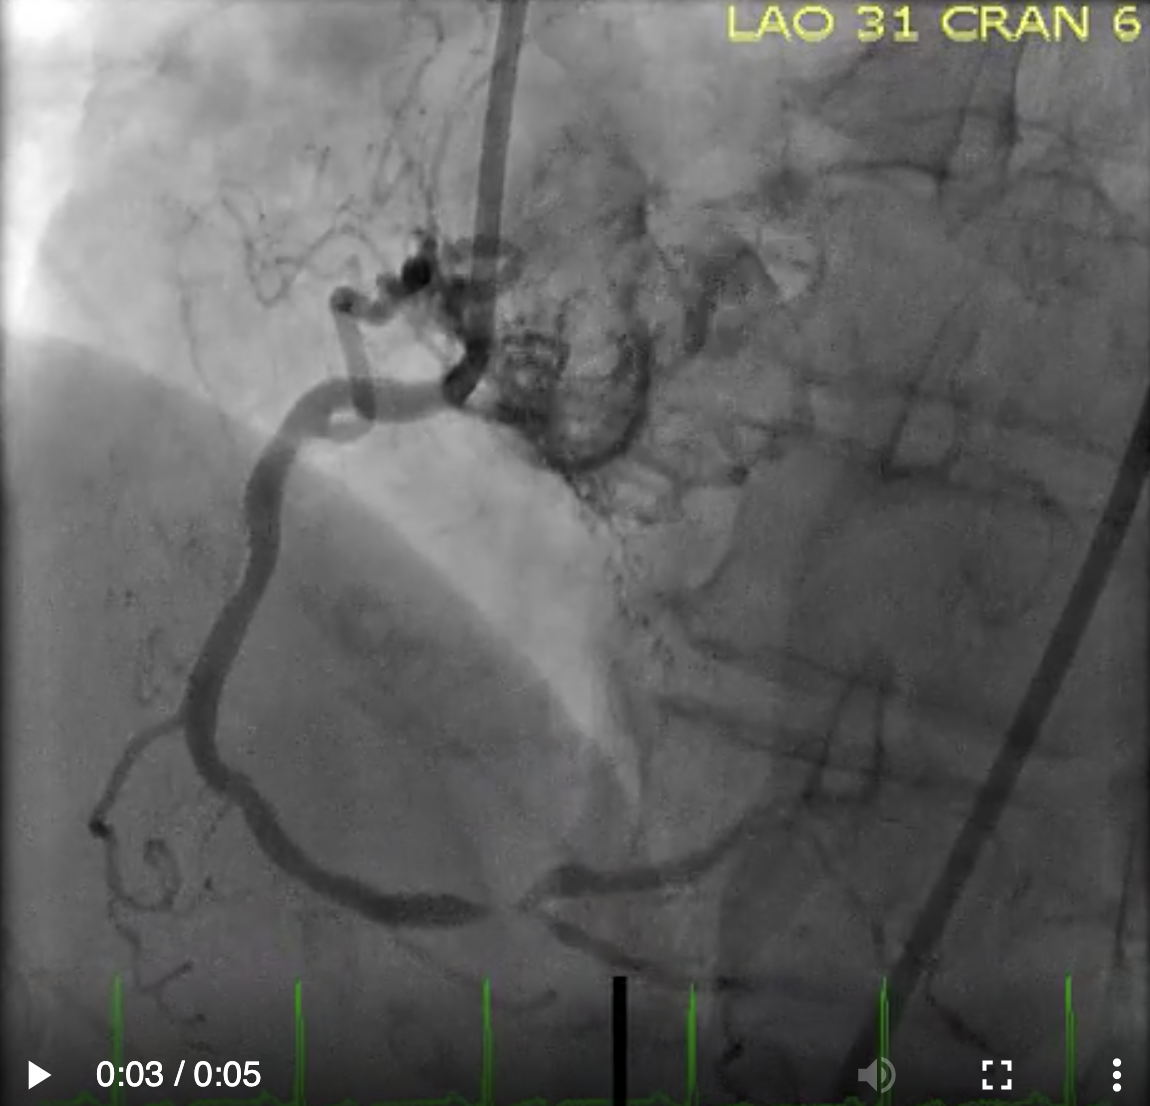

Describe the findings:

RCA dissection